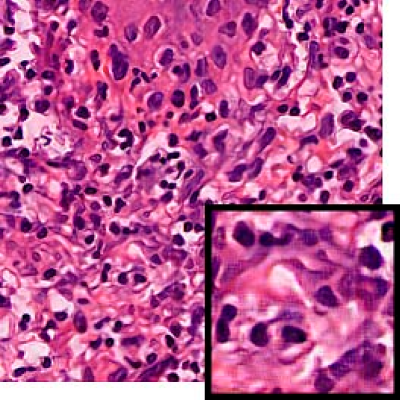

Leishmaniasis background and histology presentation. The World Health Organization (WHO) has selected cutaneous leishmaniasis as a neglected tropical disease (NTD) with growing, uncontrolled, and ignored infection affecting millions of people every year [14, 9]. It is unfortunately one of the world’s most neglected poverty-related diseases, affecting the poorest people in developing countries and it is associated with risk factors like malnutrition, immune system deficiency, migration, inadequate education, illiteracy, gender inequality, and a shortage of services [1]. Furthermore, only eight countries in the world contribute to 90% of leishmaniasis cases: Afghanistan, Algeria, Brazil, Iran, Pakistan, Peru, Saudi Arabia, and Syria [12]. It is a vector-borne infection caused by the protozoan parasite Leishmania. The vector is the female sand-fly. The lesions of cutaneous leishmaniasis vary in presentation ranging from a single self-limited skin lesion to multiple large destructive and ulcerated lesions on mostly the exposed parts of the body such as face, forearms, and lower legs [2]. Skin biopsy is considered the gold standard method for confirmation of diagnosis. The presence of large epitheloid granulomas and small hematoxylinophilic LD bodies (that are round, uniform in appearance, intracytoplasmic and sometimes distributed around the outer rim of the vacuoles) is critical for diagnosis and confirmation of leishmaniasis [4]. Large granulomas are visible at 10X but the smaller hematoxylinophilic bodies (around 3-4mm in size) are usually visible at 40X and can easily be missed if they are few in number, leading to misdiagnosis. Specialized dermatopathologists are the only ones who can diagnose these accurately based on patient history, clinical features, and laboratory diagnosis. It is thus critical to share the digitized slides of these cases from rural poor remote areas with dermatopathologists (mostly residing in urban centers) for quick diagnosis and accurate management of the patient.

We demonstrate our WSI creation workflow on Leishmaniasis cases, as shown in Figures 1 and 4. An expert pathologist reviewed the cases and annotated granulomas as well as LD bodies on the stitched images and our generated images in Figure 4. To show generalizability of our approach, we also show results on core biopsies of breast, duodenum, stomach, liver, and lymph nodes (Figure 5).